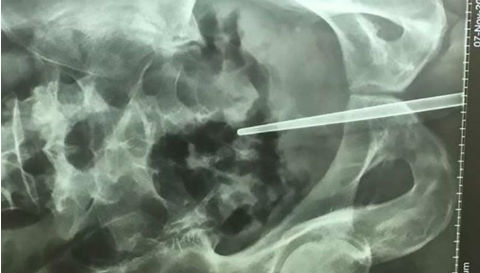

Hy hữu: Nhét đũa vào dương vật khi bạn nhậu thách đố

Trong lúc nhậu với nhóm bạn, người đàn ông dùng đũa dài 12 cm tự chọc vào dương vật của mình.